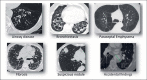

Endoscopic lung volume reduction (ELVR) is being adopted as a treatment option for carefully selected patients suffering from severe emphysema. ELVR with the one-way endobronchial Zephyr valves (EBV) has been demonstrated to improve pulmonary function, exercise capacity, and quality of life in patients with both heterogeneous and homogenous emphysema without collateral ventilation. In this "expert best practices" review, we will highlight the practical aspects of this therapy. Key selection criteria for ELVR are hyperinflation with a residual volume >175% of predicted, forced expiratory volume <50% of predicted, and a 6-min walking distance >100 m. Patients with repeated infectious complications, severe bronchiectasis, and those with unstable cardiovascular comorbidities should be excluded from EBV treatment. The procedure may be performed with either conscious sedation or general anesthesia and positive pressure mechanical ventilation using a flexible endotracheal tube or a rigid bronchoscope. Chartis and EBV placement should be performed in 1 procedure when possible. The sequence of valve placement should be orchestrated to avoid obstruction and delivery of subsequent valves. If atelectasis has not occurred by 1 month after procedure, evaluate valve position on CT and consider replacing the valves that are not optimally positioned. Pneumothorax is a common complication and typically occurs in the first 2 days following treatment. A management algorithm for pneumothorax has been previously published. Long-term sequelae from EBV therapy do occur but are easily manageable.